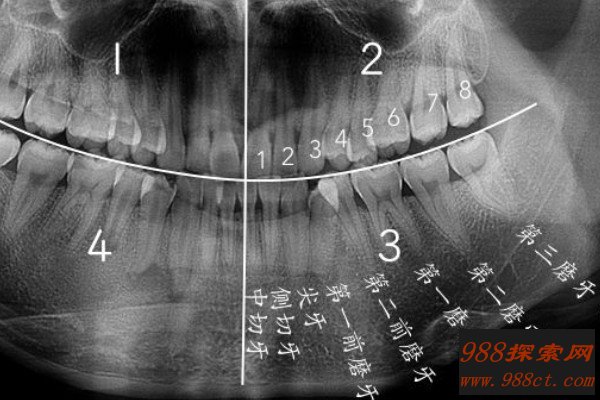

智齿是人类口腔内牙槽骨上最里面的第三颗磨牙,由于它经常会产生疼痛感,很多人选择将其拔掉,但部分人表示拔智齿后悔死了,那么这是为什么呢?快和小编去看看吧。

人在成年之后一般都会长智齿,在其生长期间可能会出现牙龈肿痛的情况,严重影响人们的日常生活,所以很多医生都建议将其拔掉,但总有人会因为拔掉后出现的不良反应而后悔。事实上,智齿对人的危害没有那么大,如果其生长状态比较良好,则没有强行拔除的必要,除非是畸形智齿。